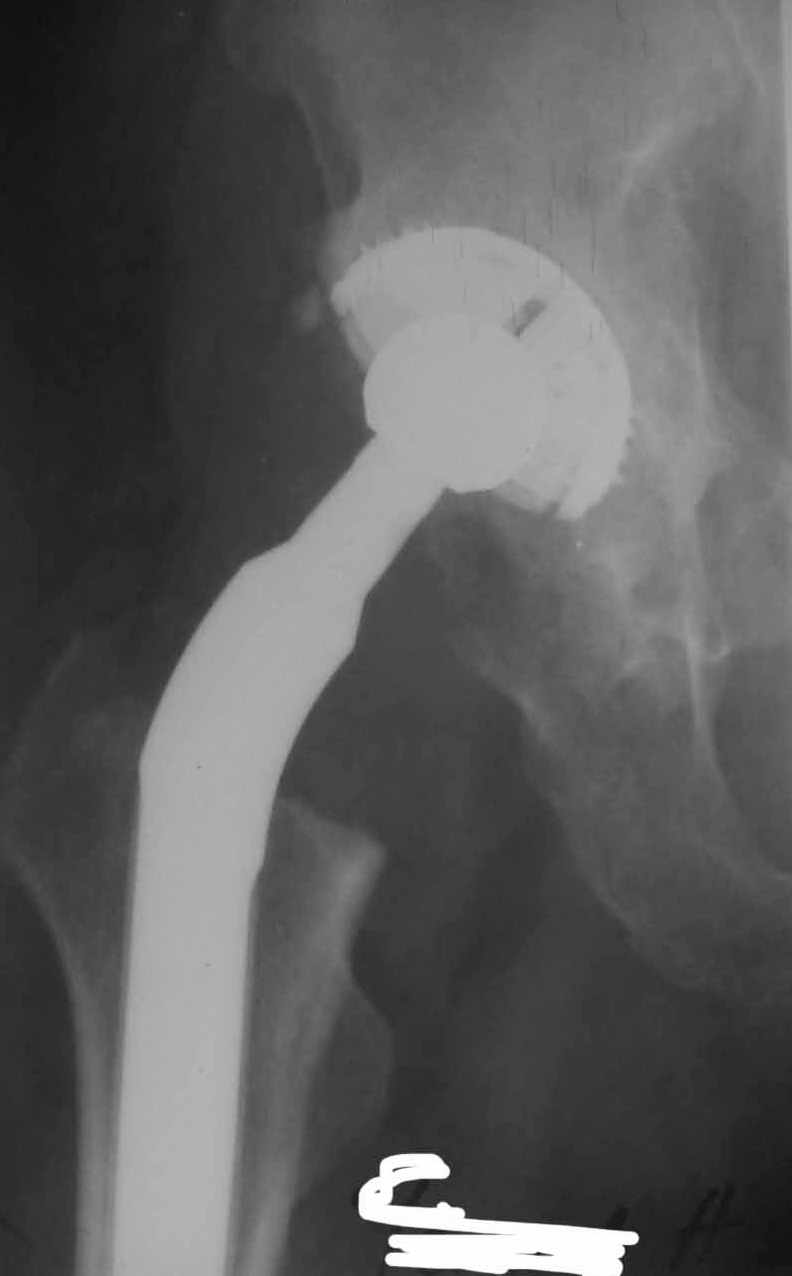

Сан Саныч,

Консультировать вывихи по рентгенограммам, не зная хода операции, дело не очень благодарное. Я думаю, что с датой операции Вы ошиблись и это был 2004 год? Тем не менее. Настораживают два фактора. Первое - не видно большого вертела. Если с мышцами обошлись грубо и их отсекли, то это очень грустно и нужна "связанная" пара, т.н. "constrain cup". Смущает хорошо прослеживаемый малый вертел и небольшая ретроверсия чашки. Возможно это (избыточная ретроверсия ножки и чашки) могло послужить причиной вывиха. Обычно гипсовая повязка после операции не накладывается, значит, были глубокие сомнения у оперировавшего хирурга. В этом случае - ревизия с перестановкой как минимум - ножки, а как максимум - обоих компонентов.

Но желательно бы знать ход операции.